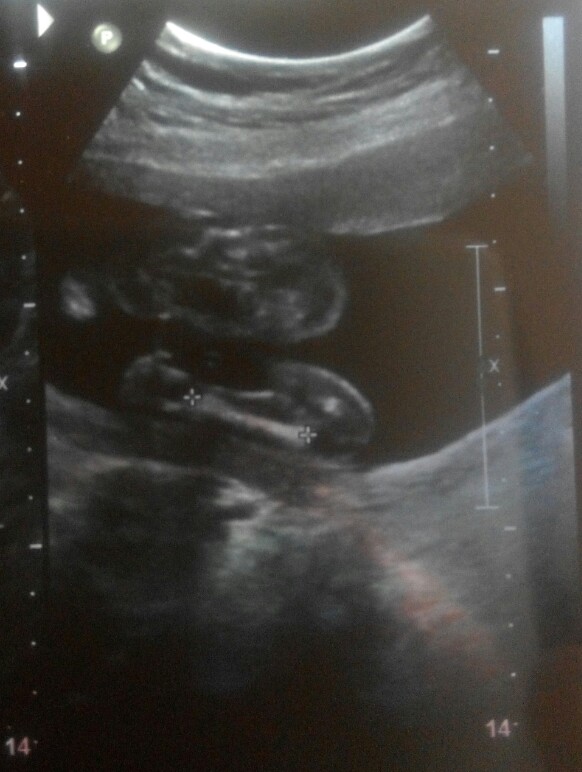

Below are ultrasound scan (19 week) of our kid. Can you please help us know if is HE or SHE?